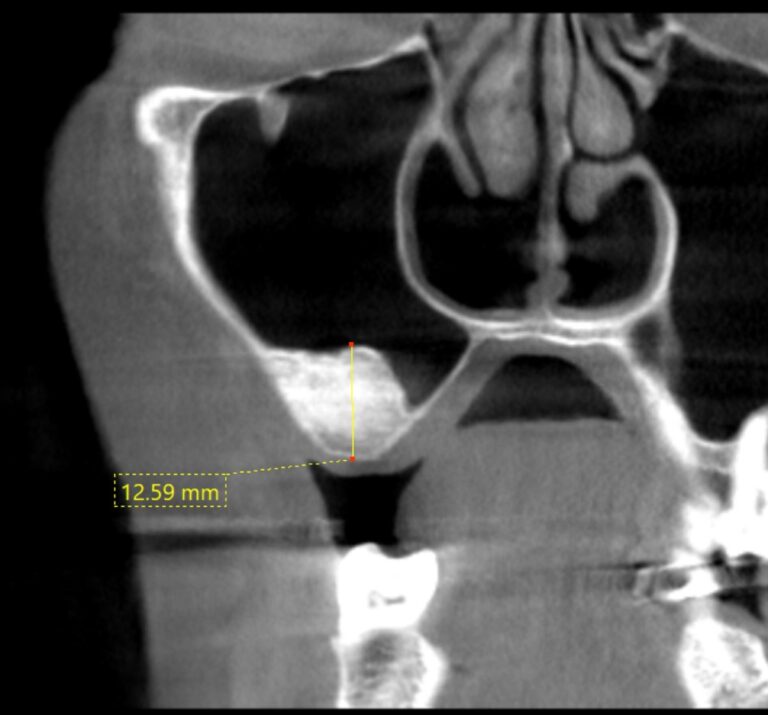

治療前

サイナスリフト GBR

インプラントを埋入する骨の厚みが十分にありません。

治療後

人工の骨を使って骨の厚みを確保し、インプラント治療を行いました。